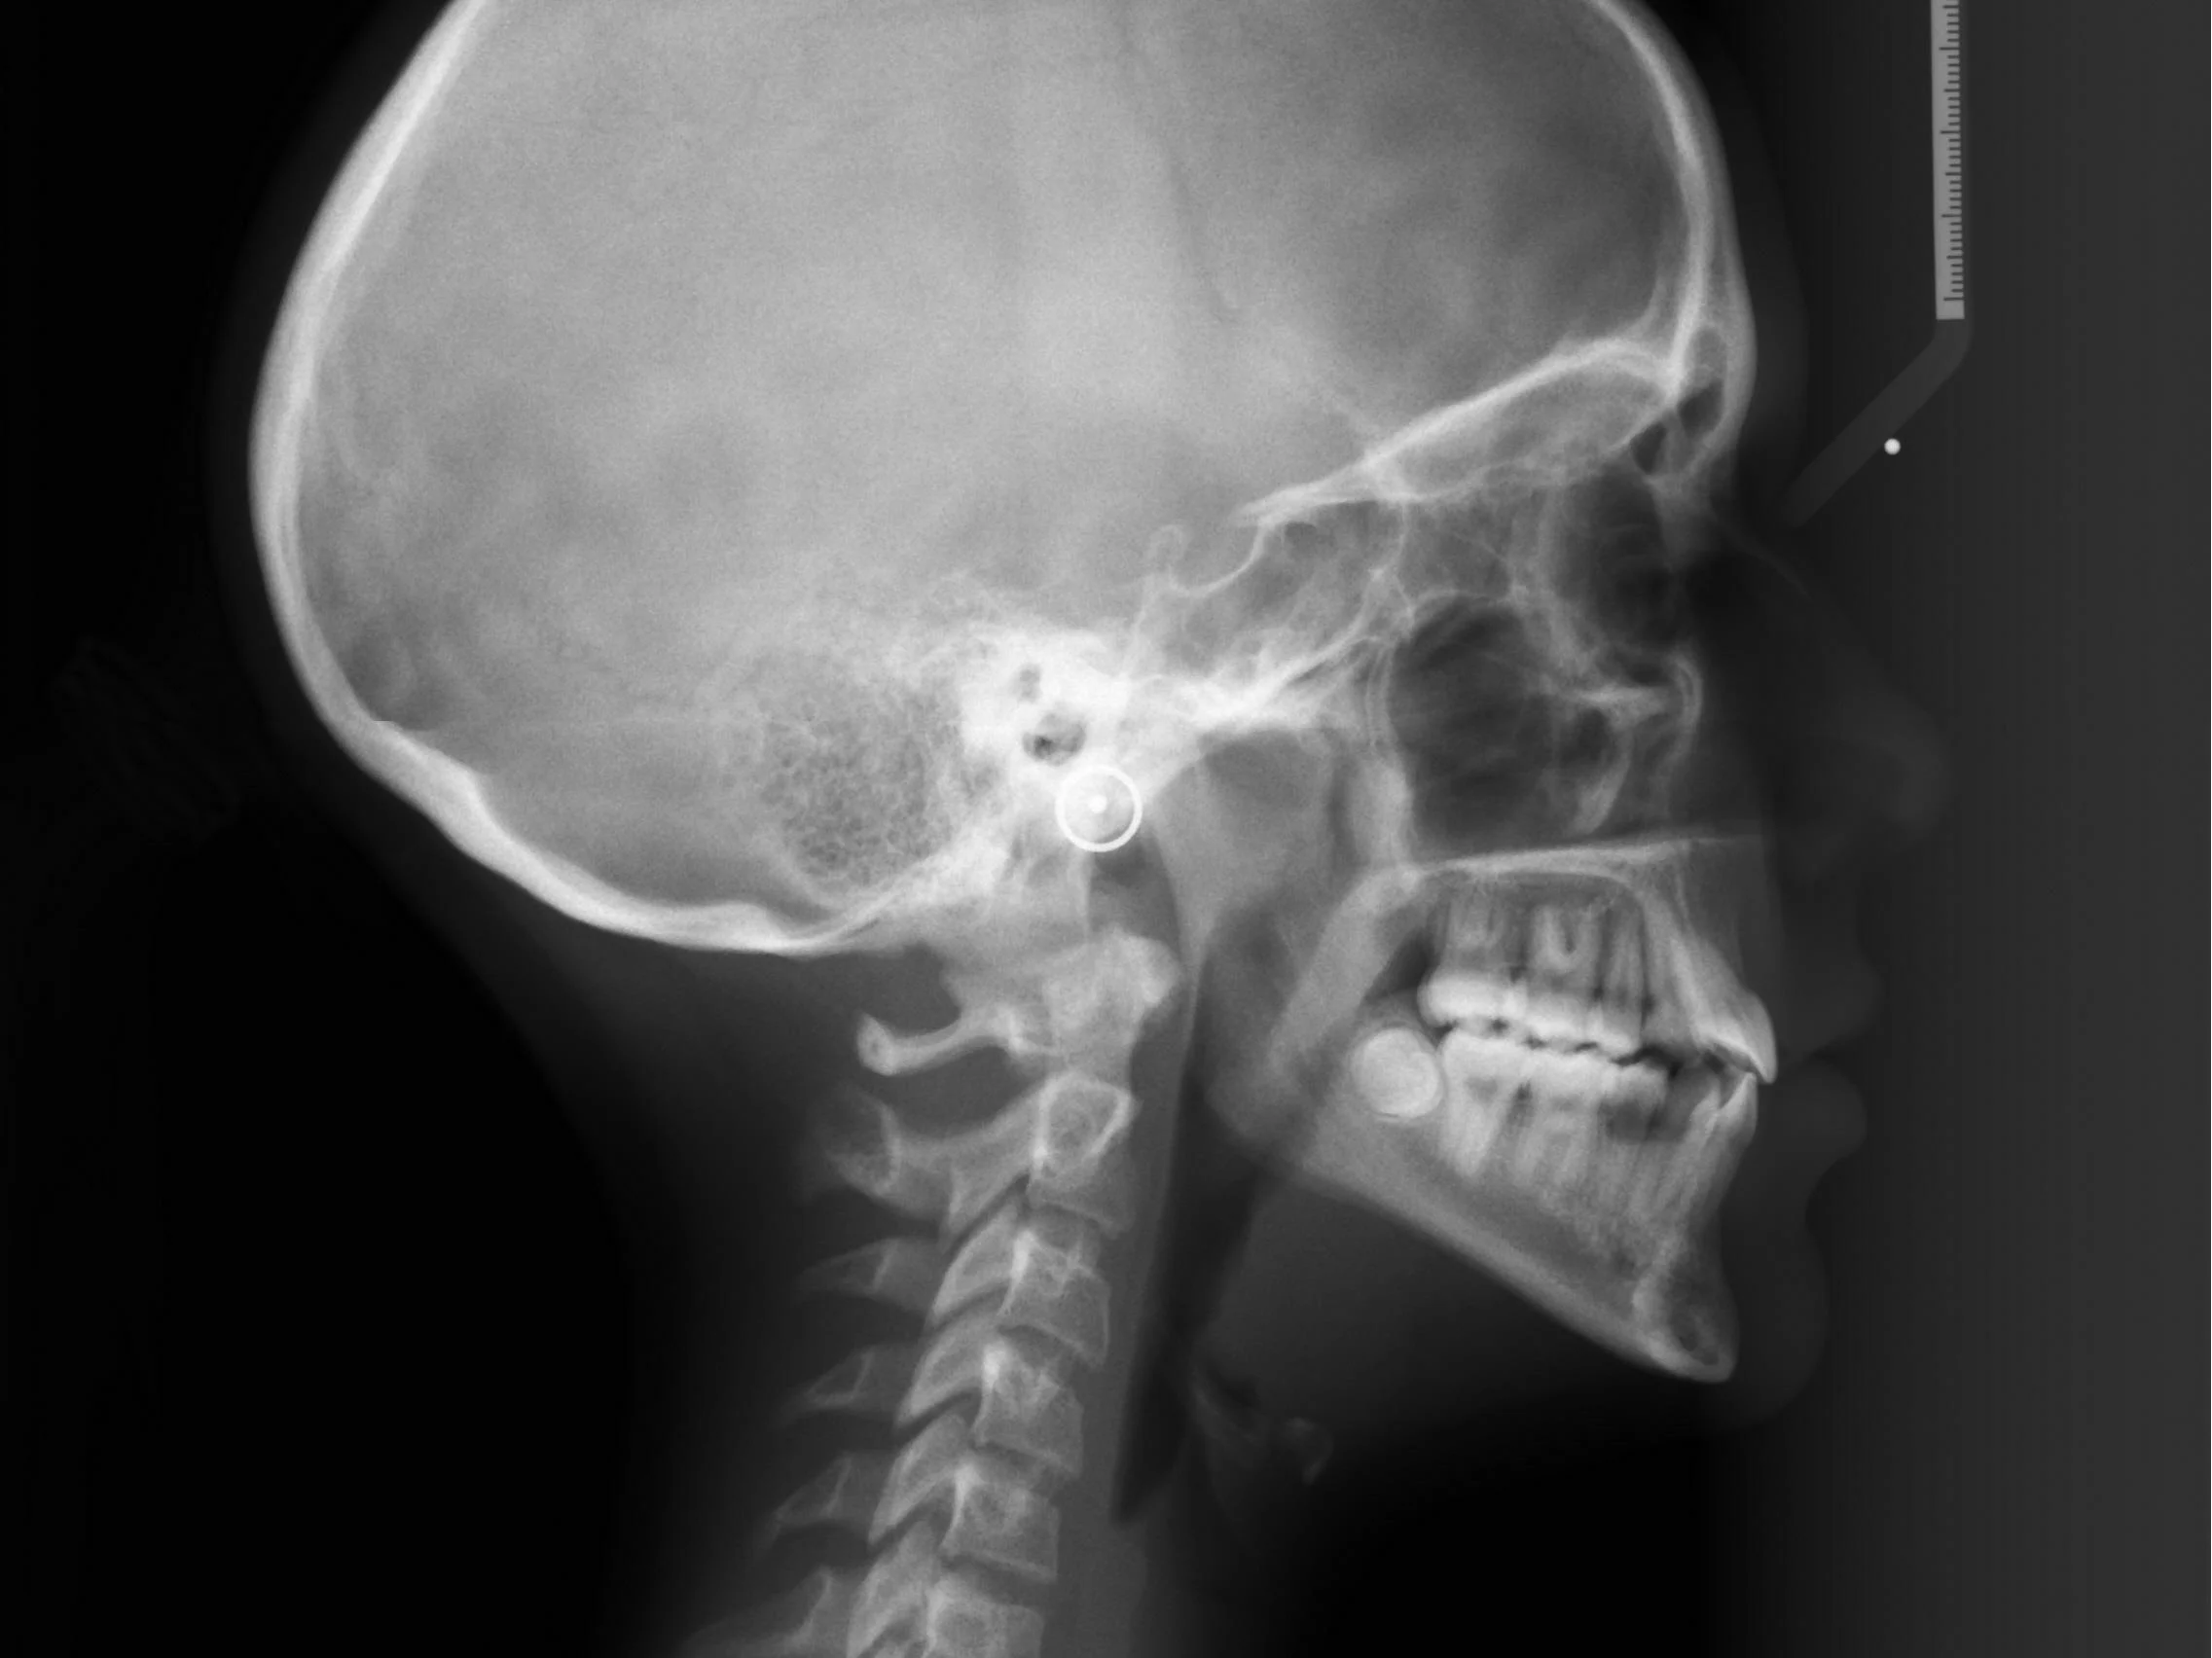

The American Association of Orthodontists (AAO) recommends that all children have a check-up with an orthodontist specialist no later than age 7.  At this time, the bite begins being establish when the first molars erupt (approximately age 6). The incisors or the front teeth have also begun to erupt at this time and problems can be detected such as crowding, habits, deep bites and some jaw discrepancies.  Although most kids do not need treatment at this time, a timely evaluation will lead to significant treatment benefits moving forward and the immediate benefit of a parent's peace of mind. Adolescents and adults with fully developed dentition can seek a consultation from an orthodontist at any time.

Records

Initial records are done to get an understanding of the malocclusion. This typically consists of x-rays, photographs, and study models of the teeth. We then use these records to finalize the treatment plan.